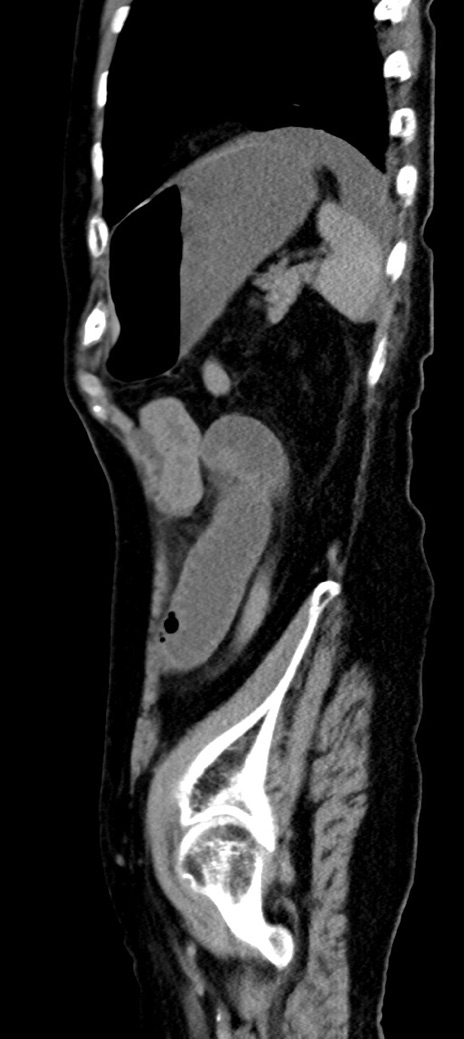

横断像

冠状断像